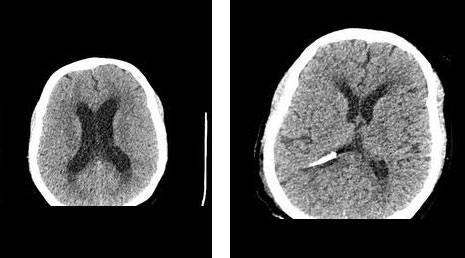

52. Subdural hematoma